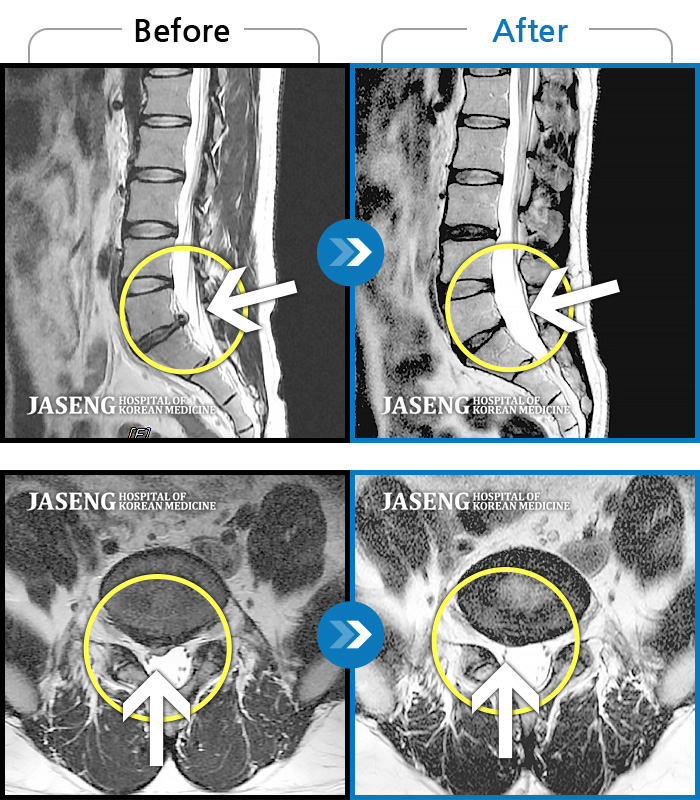

허리디스크

강남 · 강만호 원장

허리통증 및 왼쪽 다리 통증으로 운전이 불가능했습니다.

촬영시기

2023.10.16 ~ 2024.10.14

2024.10.23

조회수 457